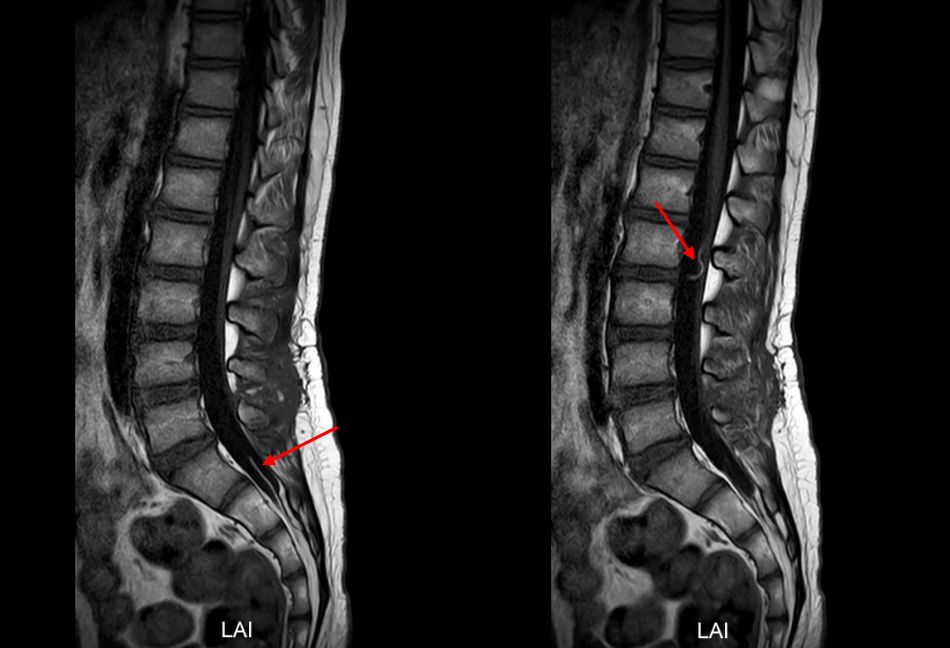

综合以上检查,诊断考虑“病毒性脑脊髓炎”。予“阿昔洛韦”抗病毒、“金璐捷”营养神经、“甲强龙”激素冲击等对症治疗15天,好转后出院。出院后继续口服“强的松”治疗1年余。出院后平时可下地行走,但未能坚持长时间,爬楼梯吃力,可短程小跑,剧烈运动或行走时间长后有腰背部疼痛、四肢酸痛,休息后可好转,感冒后症状加重,行走困难,站立不稳,伴腰背疼痛及排尿困难,有时大便失禁。感冒好转后症状可缓解,恢复至平时状态。现双下肢可行走,无腰背部疼痛、四肢酸痛,来院复查磁共振见脊髓粗细正常,未见明显异常信号(图2),为进一步诊治,门诊拟“病毒性脑脊髓炎”再次收住入院。

图2. 治疗1年后复查头颅及全脊髓磁共振:左侧小脑半球与前片比较异常信号基本消失。全脊髓粗细正常,未见明显异常信号。